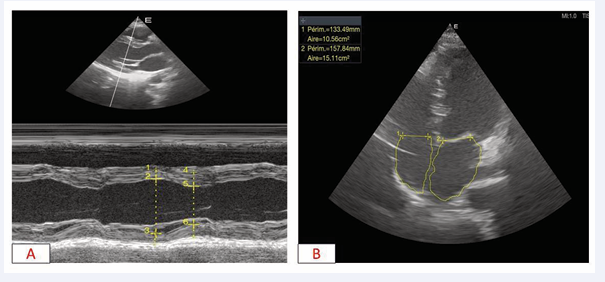

A follow-up echocardiogram showed a thrombus-free left ventricular cavity (Figure 3).

Figure 3 Transthoacic Doppler echocardiography A: long-axis para-sternal slice, absence of intraventricular thrombi B: apical 4-cavity slice, absence of intraventricular thrombi

Figure 3: Transthoacic Doppler echocardiography

A: long-axis para-sternal slice, absence of intraventricular thrombi B: apical 4-cavity slice, absence of intraventricular thrombi